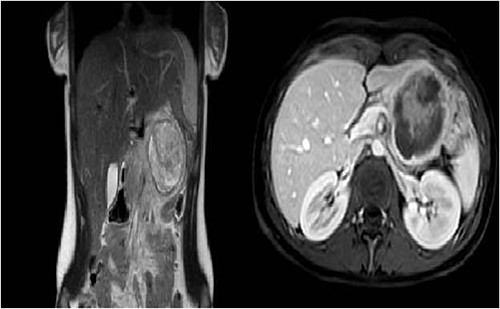

The patient was referred to the Haematology Department and underwent an MRI that showed features consistent with a diagnosis of SPT. After surgical evaluation, the patient was referred to our Department. Preoperative workup included also a thoraco-abdominal CT-scan and normal levels of pancreatic tumour markers (chromogranin A, CA19.9, CA125) (Fig. 1).